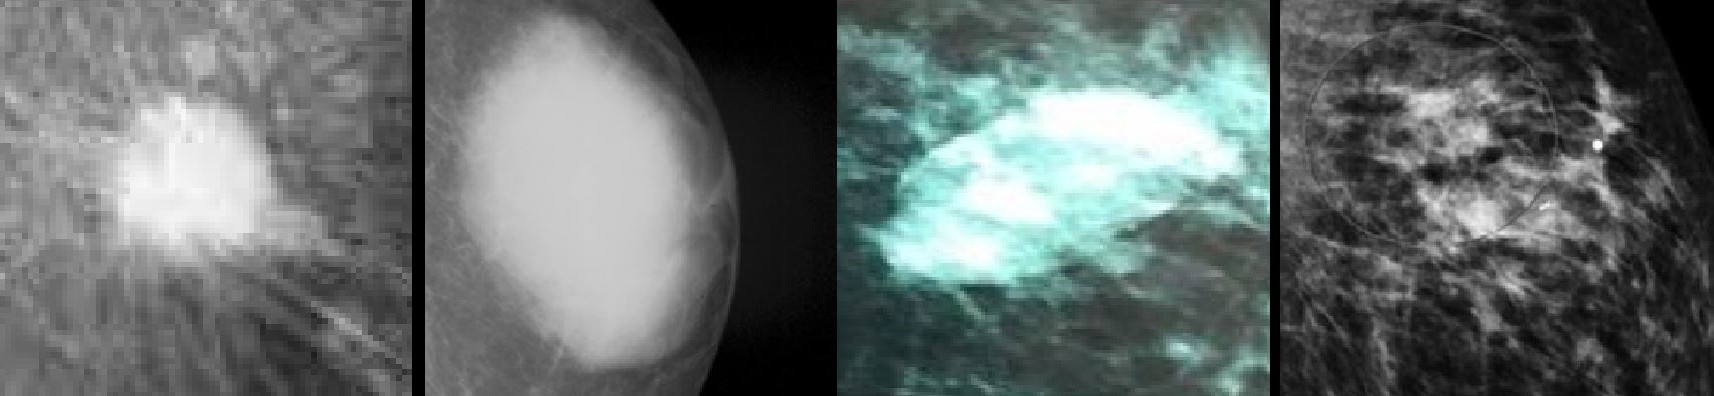

The four common descriptors in diagnostic imaging (left to right), the round, the oval the ovoidesque irregular oval and the irregular.

Reflecting the frequency with which they occur, in radiology and other forms of diagnostic imaging, the three classic shapes of “masses of interest” are round, oval and irregular but a frequent descriptor of those which often resemble ovoids is the “irregular oval” used (a little misleadingly for non-clinicians) to describe everything which tends towards being an oval but is outside the defined tolerance. The rationale in adding an adjectival “irregular” to “oval” seems to be to reflect the wide variation in the shapes, the only common characteristic being that to fit the description it must be vaguely ovoid in shape, distinguishing it not only from a round or oval but also from an irregular (ie everything else).